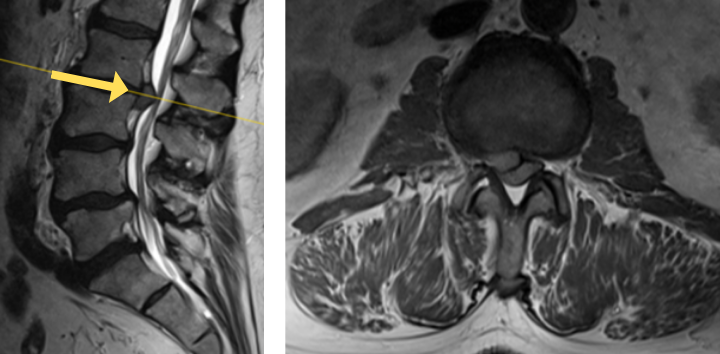

Image 3. Post-op x-rays that show L4/L5 transforaminal lumbar interbody fusion (TLIF). There was also removal the L2/L3 disc herniation but no need for instrumentation.

The herniated disc only requires decompression and removal of the herniated disc. Notice in the same flexion extension dynamic x-rays. There’s no abnormal motion at the L2/L3 level.

Dr. Imani was able to decompress both the L2/L3 level (with disc herniation removal) and the L4/L5 level. Additionally, L4/L5 level was fused using titanium screw and an expandable interbody cage. This was performed with a very small incision. The patient has no more leg pain and back pain, and is doing very well!